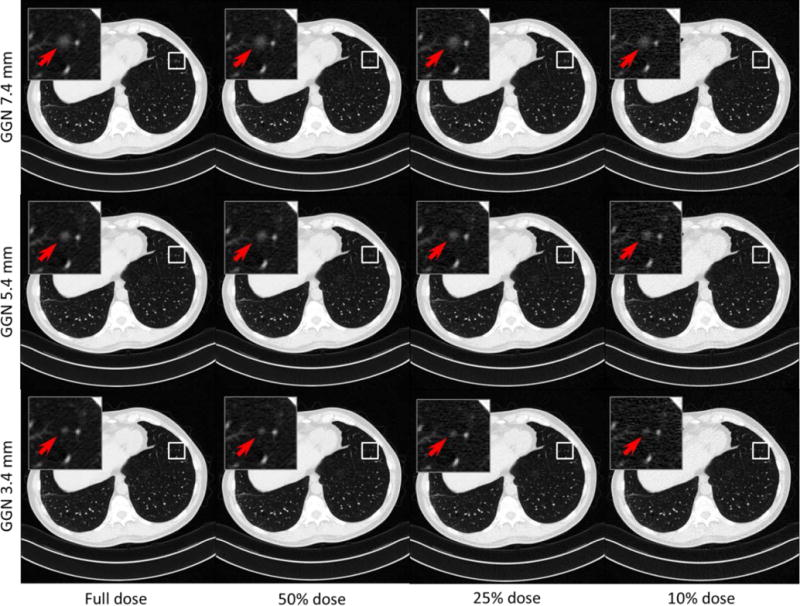

- 不同大小的肺结节&不同剂量的CT图像